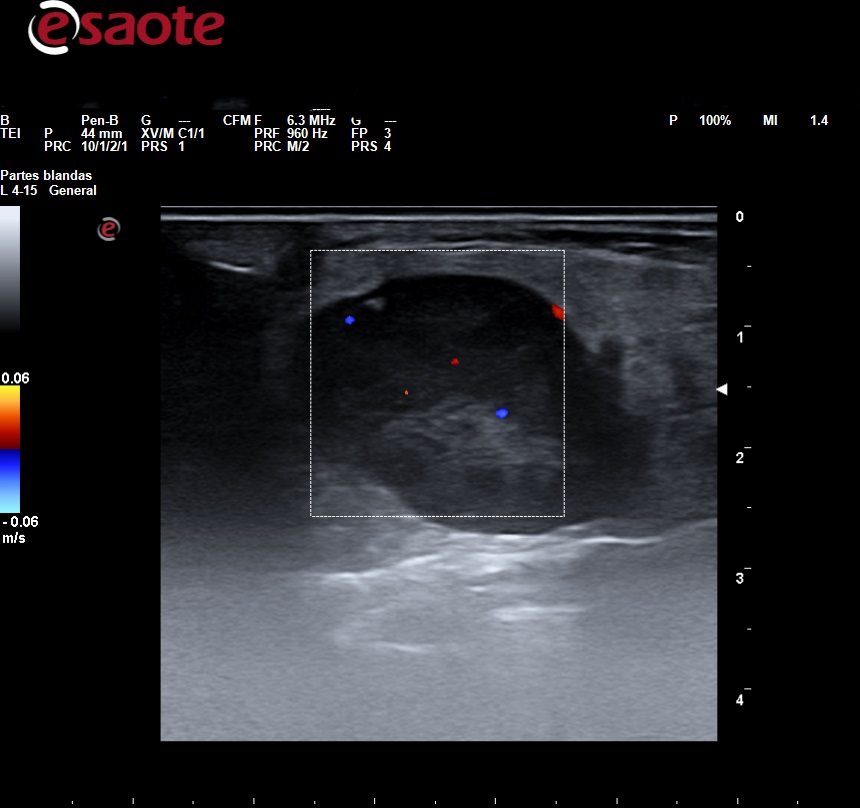

Observamos en la parótida una lesión sólida de 2,5 cm en su eje mayor, hipoecoica, heterogénea, lobulada con refuerzo acústico posterior, Doppler color presentaba vasculación escasa.